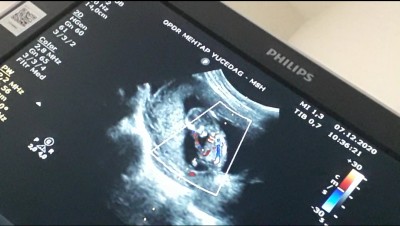

Ilk bebişim merak ediyorum sadece saglikli ve hayirli olması en önemlisi

Crl kaç canım

Evet 11 ve 12 haftalıga bakarak crl tahmin yapıyorlar

Crl yüksekse kız düşükse erkek

Haa simdi anladimm neyse saol kuzum hayırlısı olsun dr da bi pipi gibi bisey gördüde daha kesin değil işte cuma gunu gidicez bklm